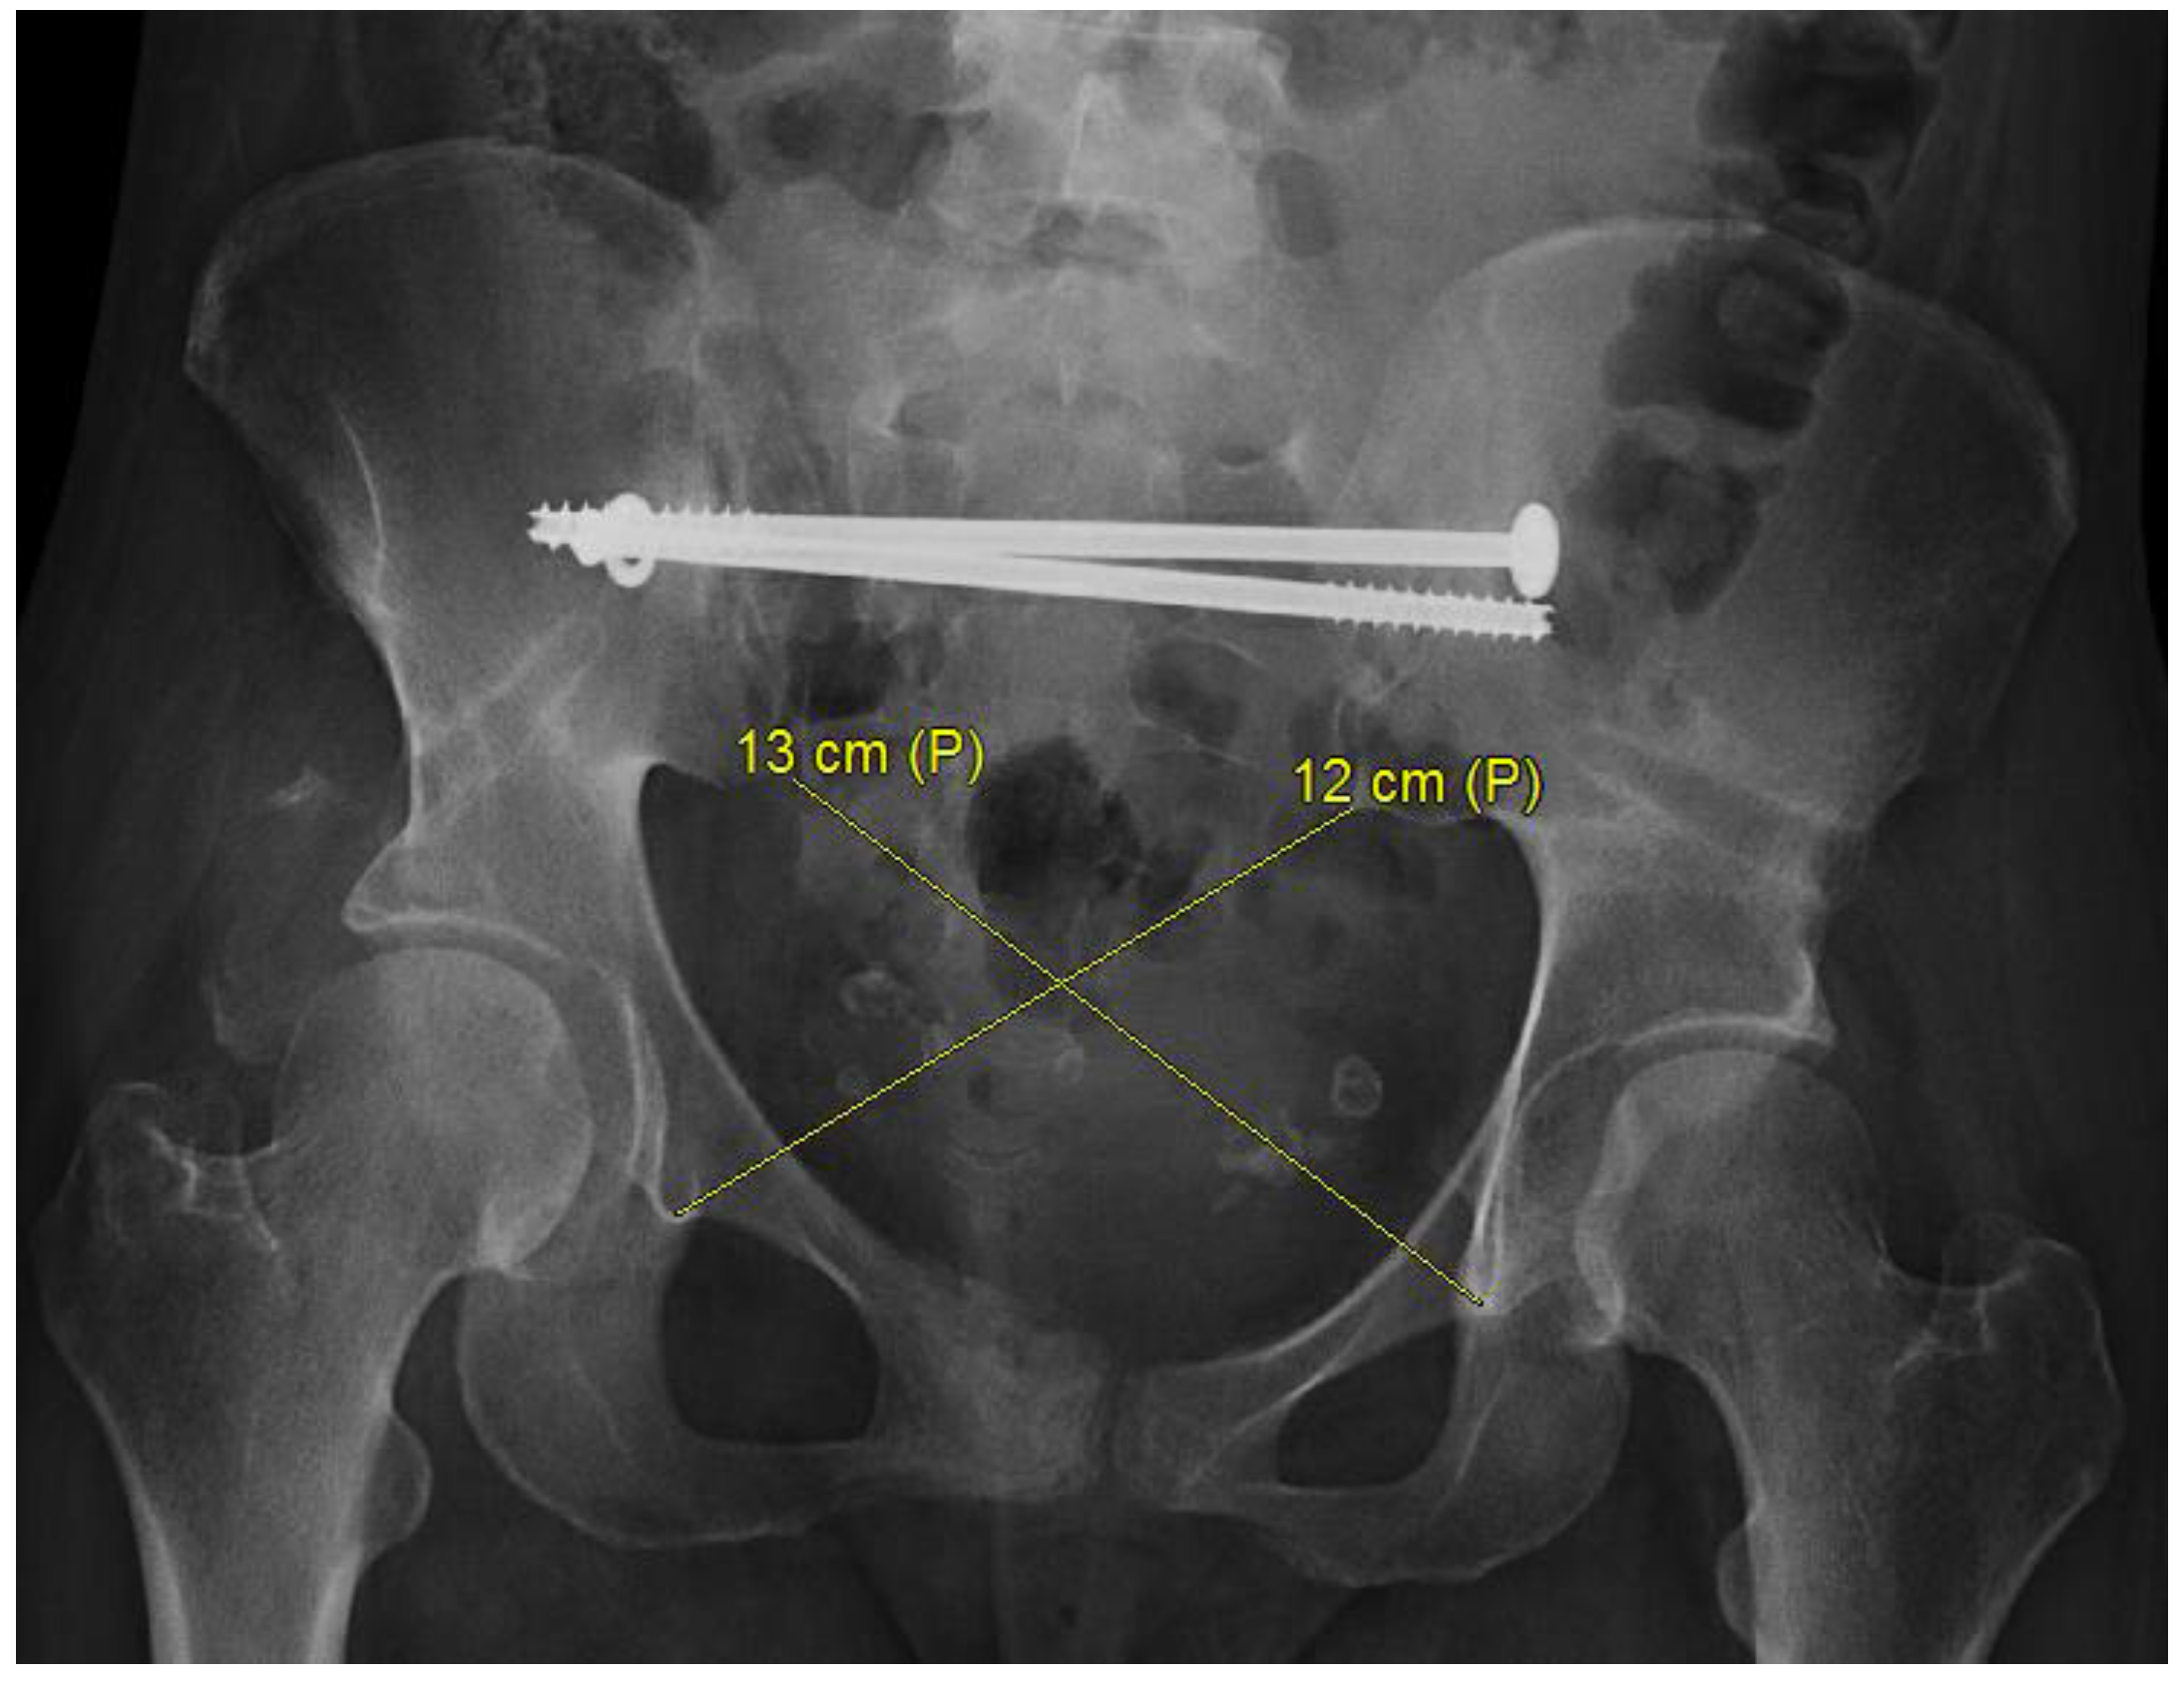

- Lu, S.; Wu, J.; Fu, B.; Dong, J.; Yang, Y.; Xin, M.; Wang, G.; He, T.-C.; Zhou, D. Transiliac Osteotomy in Surgical Management of Pelvic Post-Traumatic Malunions: A Retrospective Study. Medicine 2016, 95, e3144. [Google Scholar] [CrossRef]

- Herteleer, M.; Thüroff, J.; Rommens, P.M. Single stage reconstruction of a neglected open book pelvic injury with bladder herniation into the upper thigh: A case-report. Arch. Orthop. Trauma Surg. 2021, 141, 855–859, Correction in Arch. Orthop. Trauma Surg. 2021, 141, 1629. [Google Scholar] [CrossRef]

- Fang, C.; Alabdulrahman, H.; Pfeifer, R.; Tarkin, I.S.; Pape, H.-C. Late reconstruction of severe open-book deformities of the pelvis—Tips and tricks. Int. Orthop. 2017, 41, 1777–1784. [Google Scholar] [CrossRef] [PubMed]